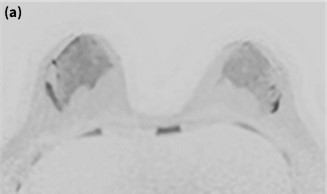

8. SIGNA™ Voyagerを用いた乳房MRI検査の有用性

当院の精査で撮像した現行の他社装置3T とSIGNA™ Voyager 1.5Tの乳房DWI(b値1000)の画像をFig.8に示す。異なる被検者ではあるが、SIGNA™ Voyagerでは両側乳房の脂肪を均一に抑制しつつ、正常乳腺を淡く描出できており高いコントラストが得られていることがわかる。これは、ARDLによる画質改善効果だけではなく、GEHC社独自技術であるDST(内蔵Body coilと8ch Breast コイルの同時受信による深部信号強度の均一化)やAIR™ Recon(コイル毎のノイズ量に応じた信号の重みづけ)の効果、さらには左右独立して設定可能なDual shim機能による高精度なシミング効果が相まって、高画質化が実現できていると考える。 これまで、乳房MRI検査は3T装置での撮像が望ましいと認識していたが、DWIのクオリティの高さや乳房検査プロトコールほぼ全てのシーケンスにDLが適用されていることを考慮すると、1.5T装置SIGNA™ Voyagerにおいても質の高い乳房MRI検査が可能と考える。

Fig.8 Voyager1.5Tと既存3T装置の乳房DWI (b1000)の比較

(a) Voyager 1.5T装置 (b) 既存3T装置